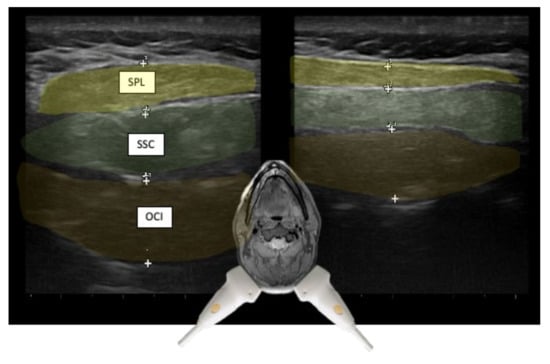

3.1. Layers and Compartments

3.2. Orientation of Layers—Reciprocal Function of Neighboring Structures

| Semispinalis capitis (SSPcap) | Extension of head | + | + | SPLcap, OCI | Strongest extensor muscle of head and neck |

| Semispinalis cervicis (SSPcer) | Extension of neck | + | + | SPLcer, TRA | |

| Splenius capitis (SPLcap) | Ipsiversion of head | ++ | ++ | major occipital nerve, SPLcap/cer, LSMcap, OCI | Prominent reduction in bulk from repeated injections possible |

| Obliquus capitis inferior (OCI) | Ipsiversion of head | +++ | +++ | SSPcap, RCM, vertebral artery, greater occipital nerve | Adjacent muscles are all extensors of the head |